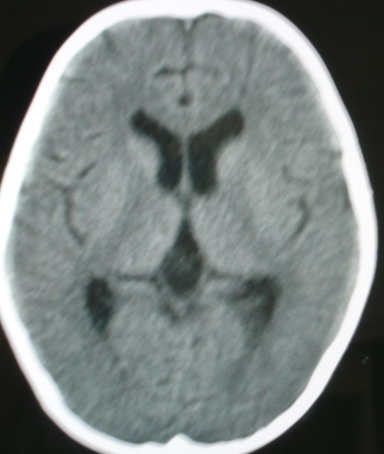

m/8y/,右侧眼睑下垂数日,发育良好,无外伤史,无头痛、恶心、呕吐,学习成绩良好。

ct意见:1、颅内血管畸形。2、右侧海绵窦血管瘤(颈内动脉海绵窦段动脉瘤)。3、脑萎缩。4、建议mr或dsa.

平扫片(骨窗未见异常)